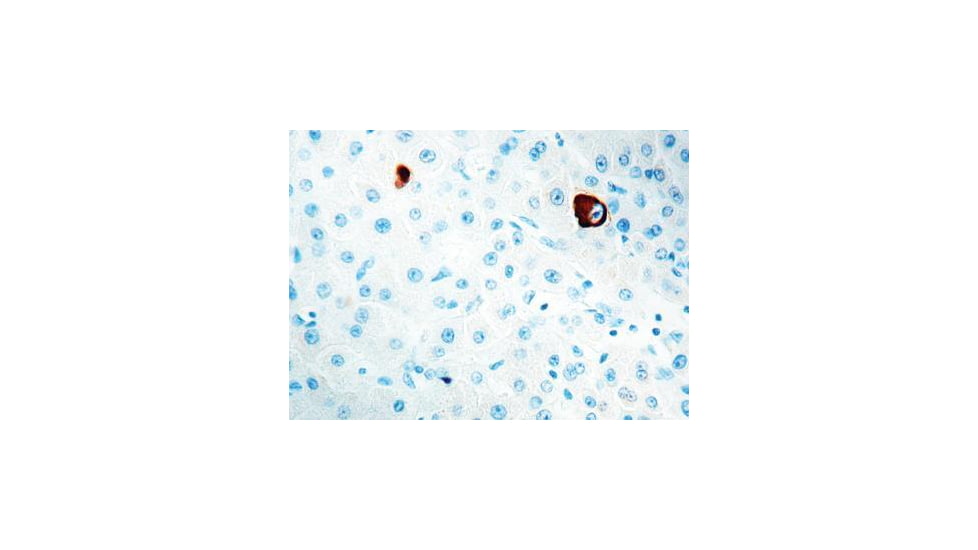

HBsAg. Clone number 3E7, This antibody stains the cytoplasm of antigen-positive liver cells in patients with Type B viral hepatitis. This antibody reacts with the ?a? determinant present on the HBsAg subtypes ayw1, ayw2, ayw3, ayw4, ayr, adw2, adw4 and adr. It does not react with normal tissues.